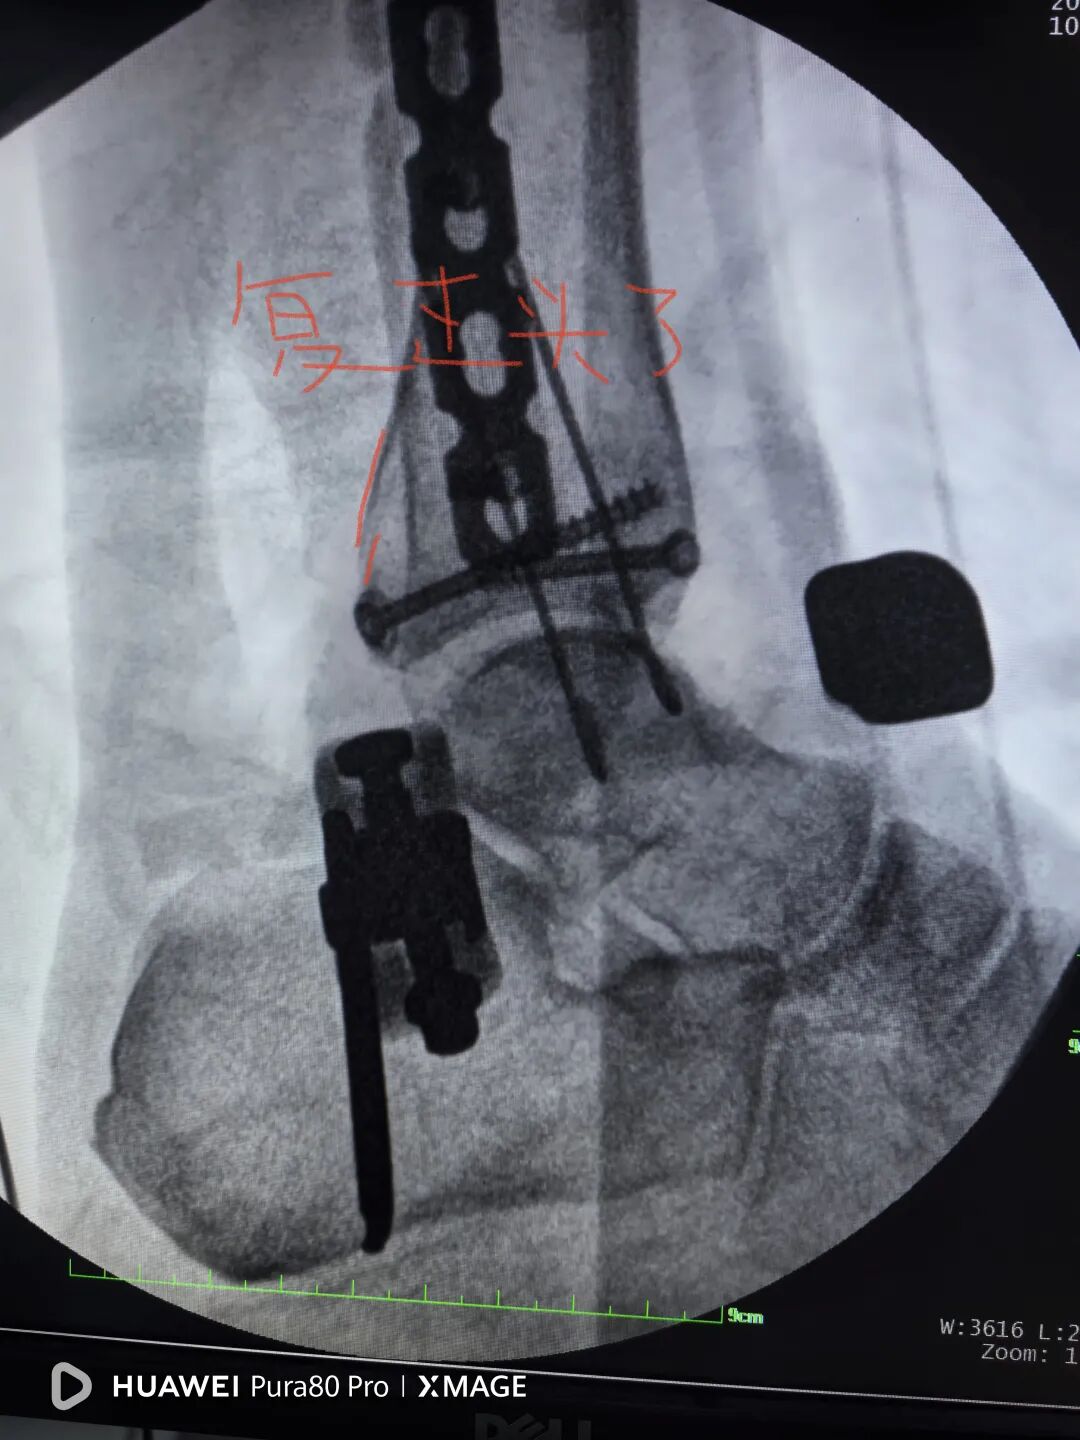

拉力钉40,拉过了,复位过头了

图片

换钉子,调整下方向

解剖复位

最后做下胫腓